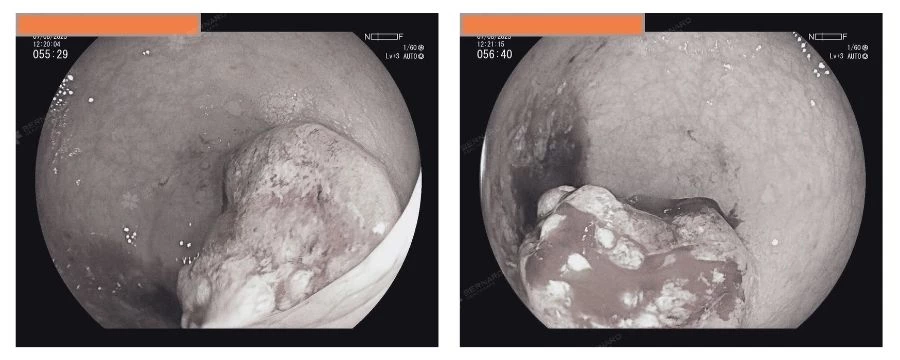

Nội soi ghi nhận dọc khung đại tràng đến trực tràng có nhiều polyp dạng có cuống, cuống ngắn và không cuống, kích thước từ 7mm đến 20 mm. Theo phác đồ điều trị, các polyp lớn được cắt bỏ ngay trong quá trình nội soi.

Đáng chú ý nhất là một khối u sùi ở trực tràng, cách bờ hậu môn 10–12cm, kích thước khoảng 3cm, lan theo chu vi lòng trực tràng, niêm mạc bở, dễ chảy máu – đặc điểm gợi ý nguy cơ ác tính cao.